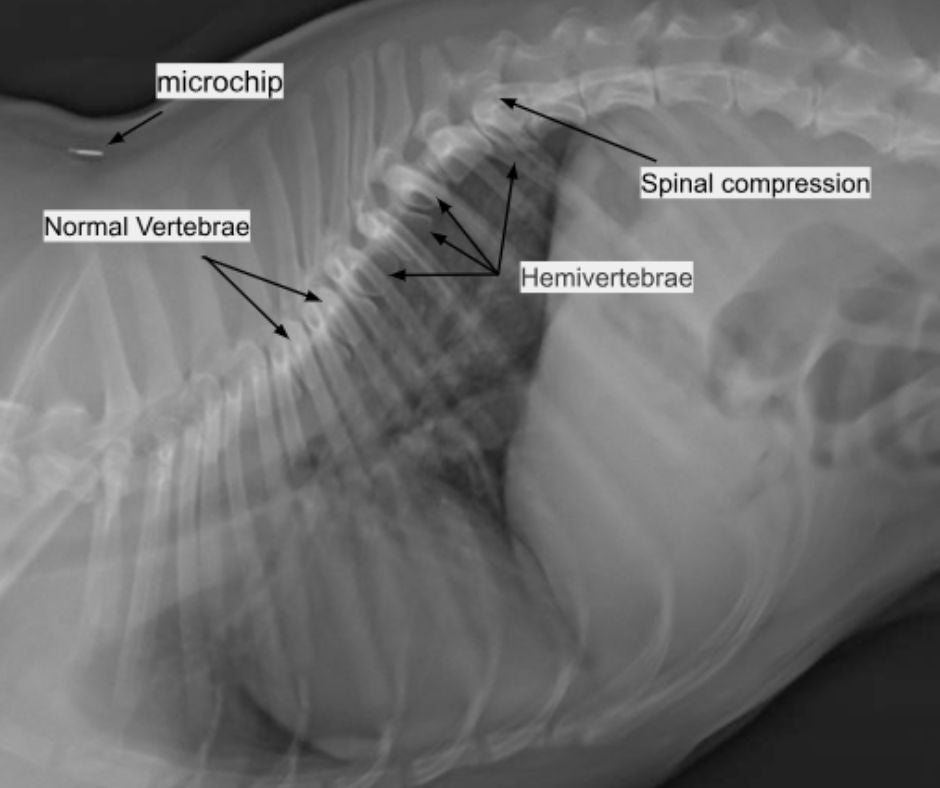

On exam, Max was very anxious, panting hard, and acutely paralyzed in his hind limbs. A neurologic exam was performed on Max to assess him for neurologic deficits and their severity. The results suggested that Max likely sustained an injury to his thoracic spine, causing the acute paralysis. This was supported by X-rays that revealed multiple abnormalities called hemivertebrae along Max’s thoracic spine and a region of spinal compression associated with the hemivertebrae, likely causing acute paralysis. A hemivertebrae is a congenital malformation of the vertebrae; normal vertebrae have a cylindrical shape but hemivertebrae often appear like trapezoids or wedges on X-rays. A hemivertebrae is typically an incidental finding on X-rays, but they can sometimes predispose patients to spinal injuries. Spinal injuries in dogs, especially in predisposed breeds like French Bulldogs and Dachshunds, can have varying prognoses. Some cases can improve with supportive care and cage rest, while others are very severe and require emergency referral to a veterinary neurologist for an MRI and surgery.

The panniculus reflex tests where the location of a spinal injury may have occurred. This test is performed by using hemostats to pinch the skin along both sides of the spine. The sharp pain of the pinch causes the skin to twitch in uninjured sections of skin along the spine. The nerves to each section of skin come directly off the spinal cord at each vertebrae; an injury along the spinal cord will cause the reflex to be absent “downstream” from the injury. In Max’s case, he had no panniculus reflex along his lumbar spine, but the reflex was intact along his thoracic spine, likely indicating a spinal injury in his lower thorax. This neurologic exam finding was supported by Max’s X-rays as there was a section of spinal compression at the T12-T13 disc space.